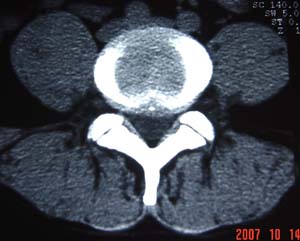

1.l4~5间盘膨出伴突出(中央型)

2.l5-s1后纵韧带钙化.

测量应该测上一层面,。支持诊断。